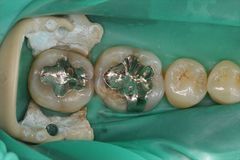

下顎左右4本の大臼歯の金属除去とセラミック修復が終わりました。2018.06.14

右下第一大臼歯の金属を除去しセラミック修復しました。2018.06.01